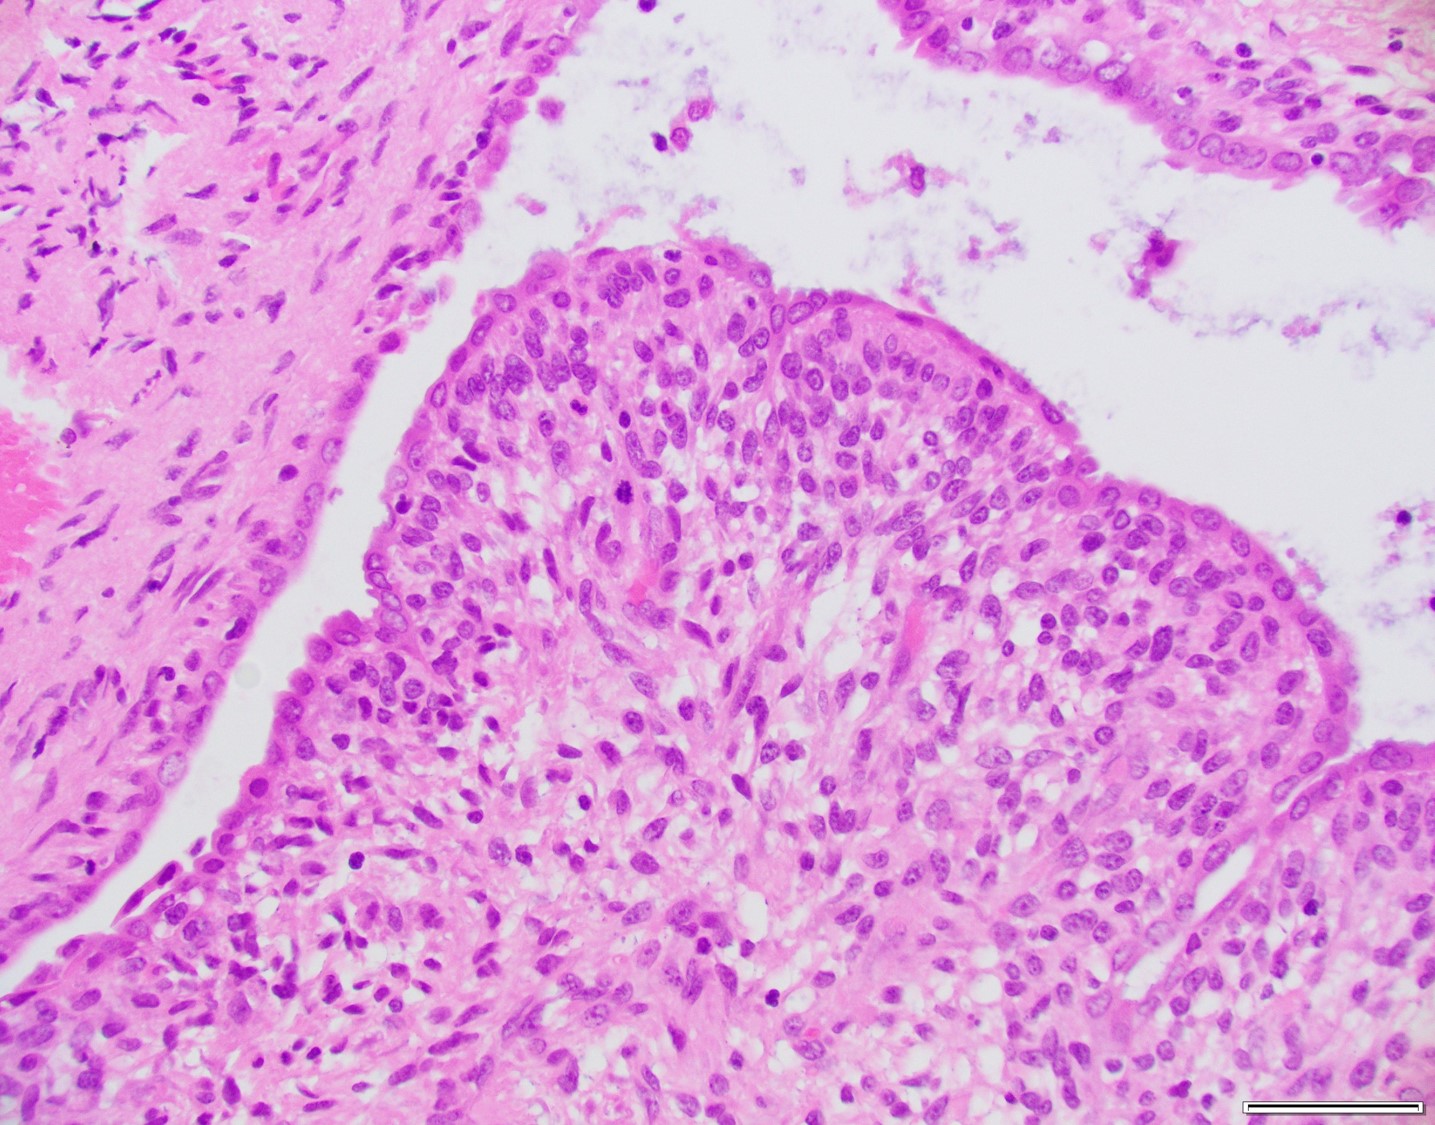

Histologically, MA usually have a phyllodes-type pattern with dilated glands lined by benign endometrial or ciliated epithelium surrounded by a distinct cuff of neoplastic stroma. This stroma is normally hypercellularand can have subtle atypical features. These tumors are often positive for CD10, ER, and PR, however there have been a subset of cases that are negative for CD10.

There are two components comprising this specimen, which are focally intimately associated with one another. The first component consists of endometrial glands and stroma surrounded by smooth muscle bundles, which in the proper clinical setting could represent a benign adenomyomatous polyp. The second component consists of a biphasic process of benign glands and stroma with a phyllodes-like architecture. The stroma surrounding the glands shows periglandular "cuffing" with very low-grade atypia. There is increased mitotic activity (greater than 2 mitoses/10 HPF) in the areas with the phyllodes-like architecture. Immunohistochemical staining showed two distinct staining patterns in the two components. The adenomyomatous polyp component showed CD10 highlighting endometrial stroma in the adenomyomatous areas with surrounding smooth muscle bundles positive for caldesmon and desmin while the stroma in the phyllodes-like area was positive for desmin and caldesmon but was negative for CD10. The patient was treated with a hysterectomy, where there was minimal focal residual disease identified.